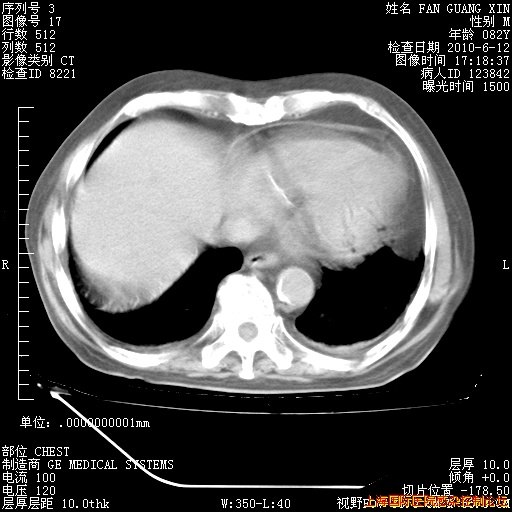

6月12日肺窗

回复

整整相隔30天的肺部CT好像有所好转啊。甲强龙减量第3天,需要观察体温。